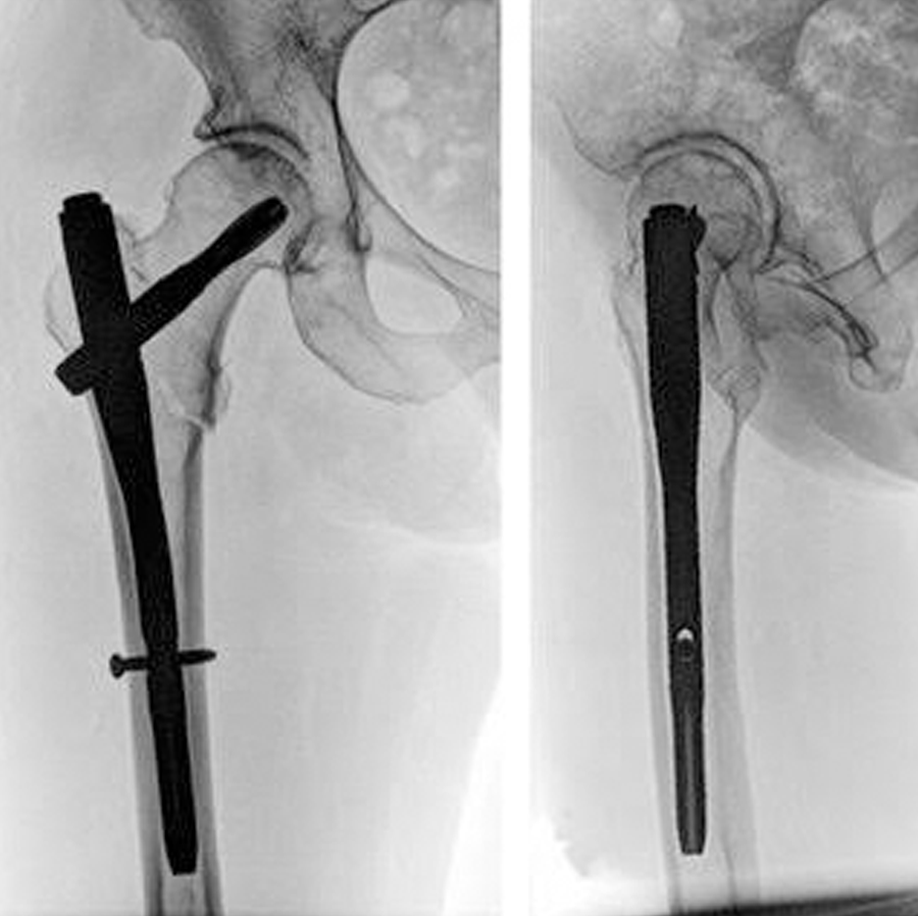

We followamerican guidelines for the treatment and Depending on the site of the fracture we decide whether to join your bones using Nail or plate and screws,or replacing the broken bone with the prosthesis.